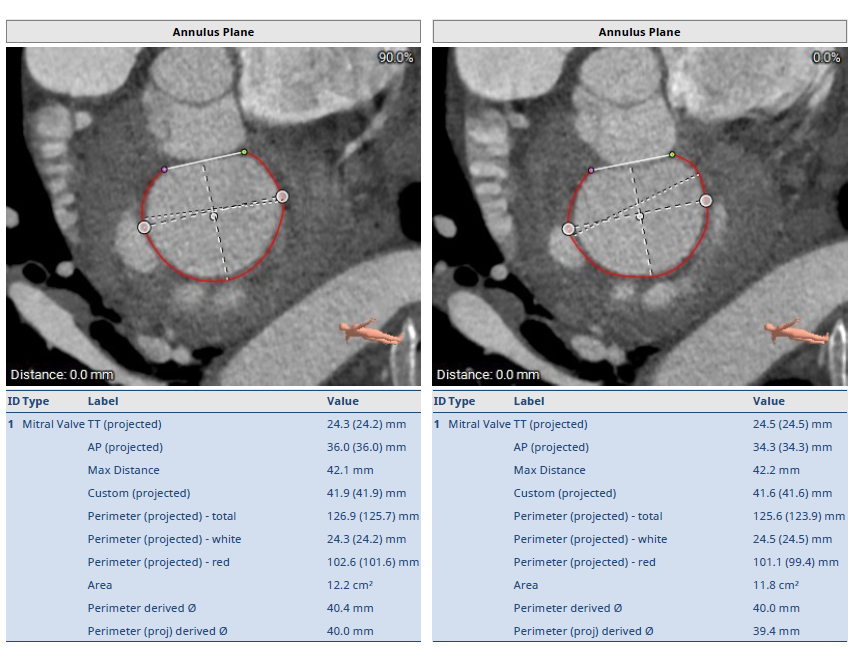

经过瑞金医院心外科MDT团队综合讨论评估该患者病情后,患者为重度FMR患者,为传统外科手术极高危患者,决定进行MitraFix®经心尖二尖瓣植入。术前心脏CTA瓣环面积折算最大直径41.5 mm 模拟植入34号二尖瓣瓣膜, 心室Neo LVOT面积可。

术前瓣环形态评估